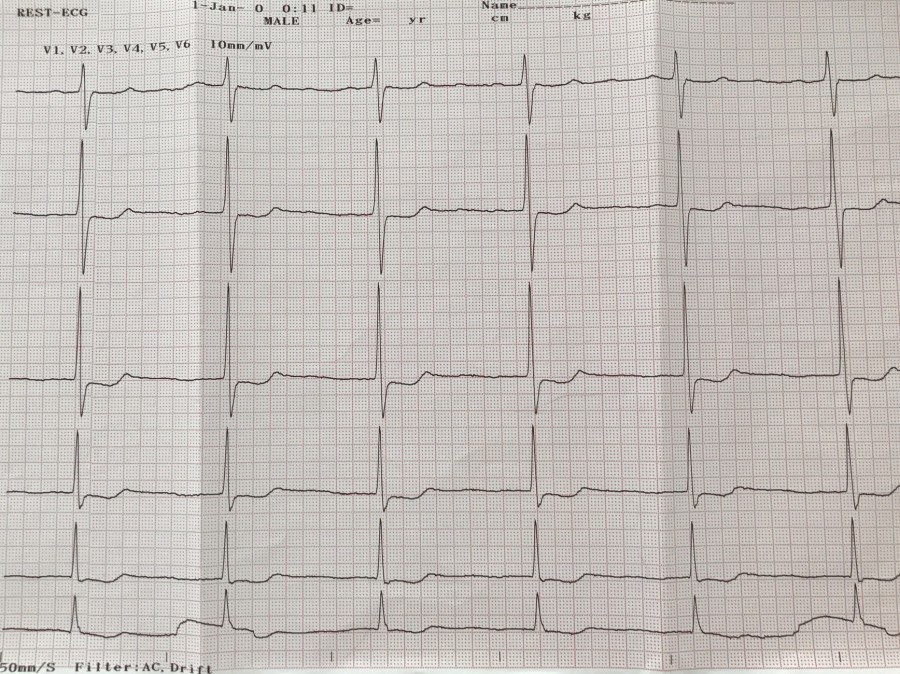

ТП 4:1. Хорошо видно в v1

ТП 2:1.

ТП, а не узловуха

ТП 1:1

Медленное ТП

ТП после РЧА WPW

Медленное ТП. Две ЭКГ одного пациента.

ЧПС 240 в мин - (второй F) - см. восходящее колено R V2

Второй F аккурат проецируется в центр QRS